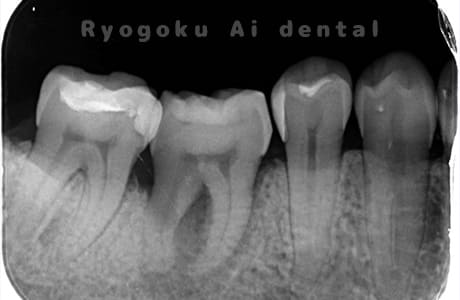

Case03

-

- 原因

- 重度カリエス、慢性根尖性歯周炎

- 治療内容

- 自家歯牙移植

- 治療費用

- 220,000円

他院で右下の根の治療を行い、セラミックを被せる説明をされていたが、根の治療が終わらないため転院された患者さんです。隣の親知らずの抜歯の必要性と、根の治療を行なっている歯牙の予後が悪いため、移植治療を提案し、右下の親知らずの抜歯と同時に、右下の奥歯(7番)への移植治療を行いました。被せ物を行う必要もなく、順調に経過してます。

<リスク・副作用>

治療後、痛みや違和感、出血、腫れなどが出る事があります。喫煙者、糖尿病などの方の場合、歯が生着しない場合があります。